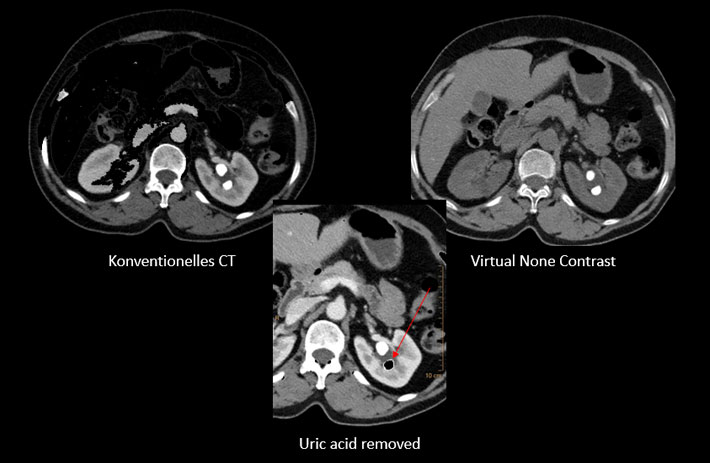

Mit dem Spektral-Detektor-CT werden Spektraldaten automatisch bei jedem Scan erfasst. Die Informationen stehen jederzeit auf der Scankonsole, der CT-Workstation sowie an jedem PACS-Arbeitsplatz zur Verfügung, sodass es nicht notwendig ist, den Patienten erneut zu scannen, bspw. wenn initial zufällige Anomalien festgestellt wurden. Dadurch profitieren Anwender durch eine höhere Diagnosesicherheit und weniger Nachuntersuchungen auf anderen bildgebenden Systemen. Unsere Fallsammlung zeigt, welchen klinischen Mehrwert der Spektral-Detektor-CT in unterschiedlichsten Anwendungsbereichen in der klinischen Routine bringt. Jede Woche gehen neue Fälle live.